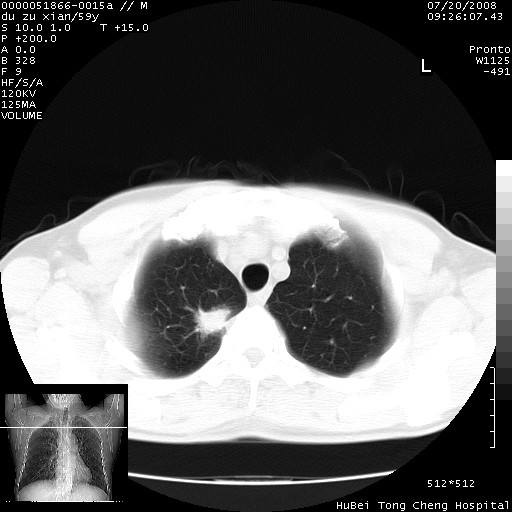

以下是引用宇宙ct在2008-8-25 23:21:00的发言:[br]右肺周围性肺癌并肋骨转移,纵隔淋巴结转移。

以下是引用zsl6918在2008-8-25 22:40:00的发言:[br]右肺周围性肺癌并肋骨转移,纵隔淋巴结转移。

以下是引用zy_zj在2008-8-26 15:24:00的发言:[br]单从病变本身,我倾向良性炎性病变,但肋骨转移了,所以说是考虑右肺周围性肺癌并肋骨、纵隔淋巴结转移可能性大。